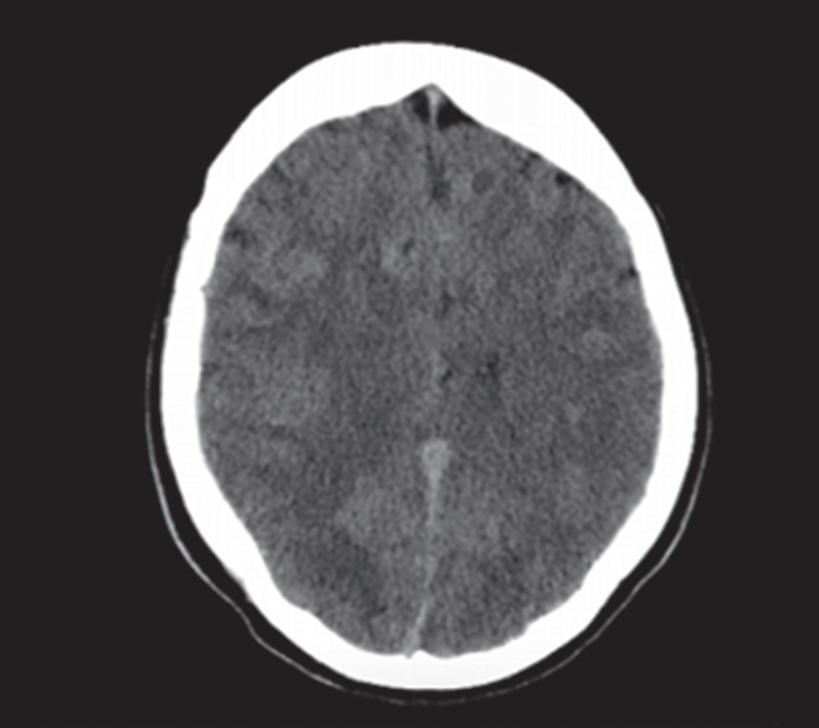

Em virtude de as manifestações clínicas não serem exclusivas das MAVs, a tomografia computadorizada do crânio sem contraste

é geralmente o primeiro exame realizado na investigação diagnóstica. Algumas alterações presentes nessa tomografia, associadas à história clínica do paciente podem direcionar a suspeição diagnóstica; são eles: pacientes jovens com hemorragia intraparenquimatosa lobar espontânea, sangramento inexplicável intraventricular ou subaracnóideo, presença de calcificações curvilíneas ou salpicadas, ou imagens serpiginosas espontaneamente hiperdensas, que podem corresponder a vasos anômalos integrantes do nidus, a veias de drenagem ou a artérias nutridoras dilatadas. Embora a angiotomografia possibilite uma melhor visualização das estruturas vasculares, a ressonância magnética em contrapartida, permite melhor